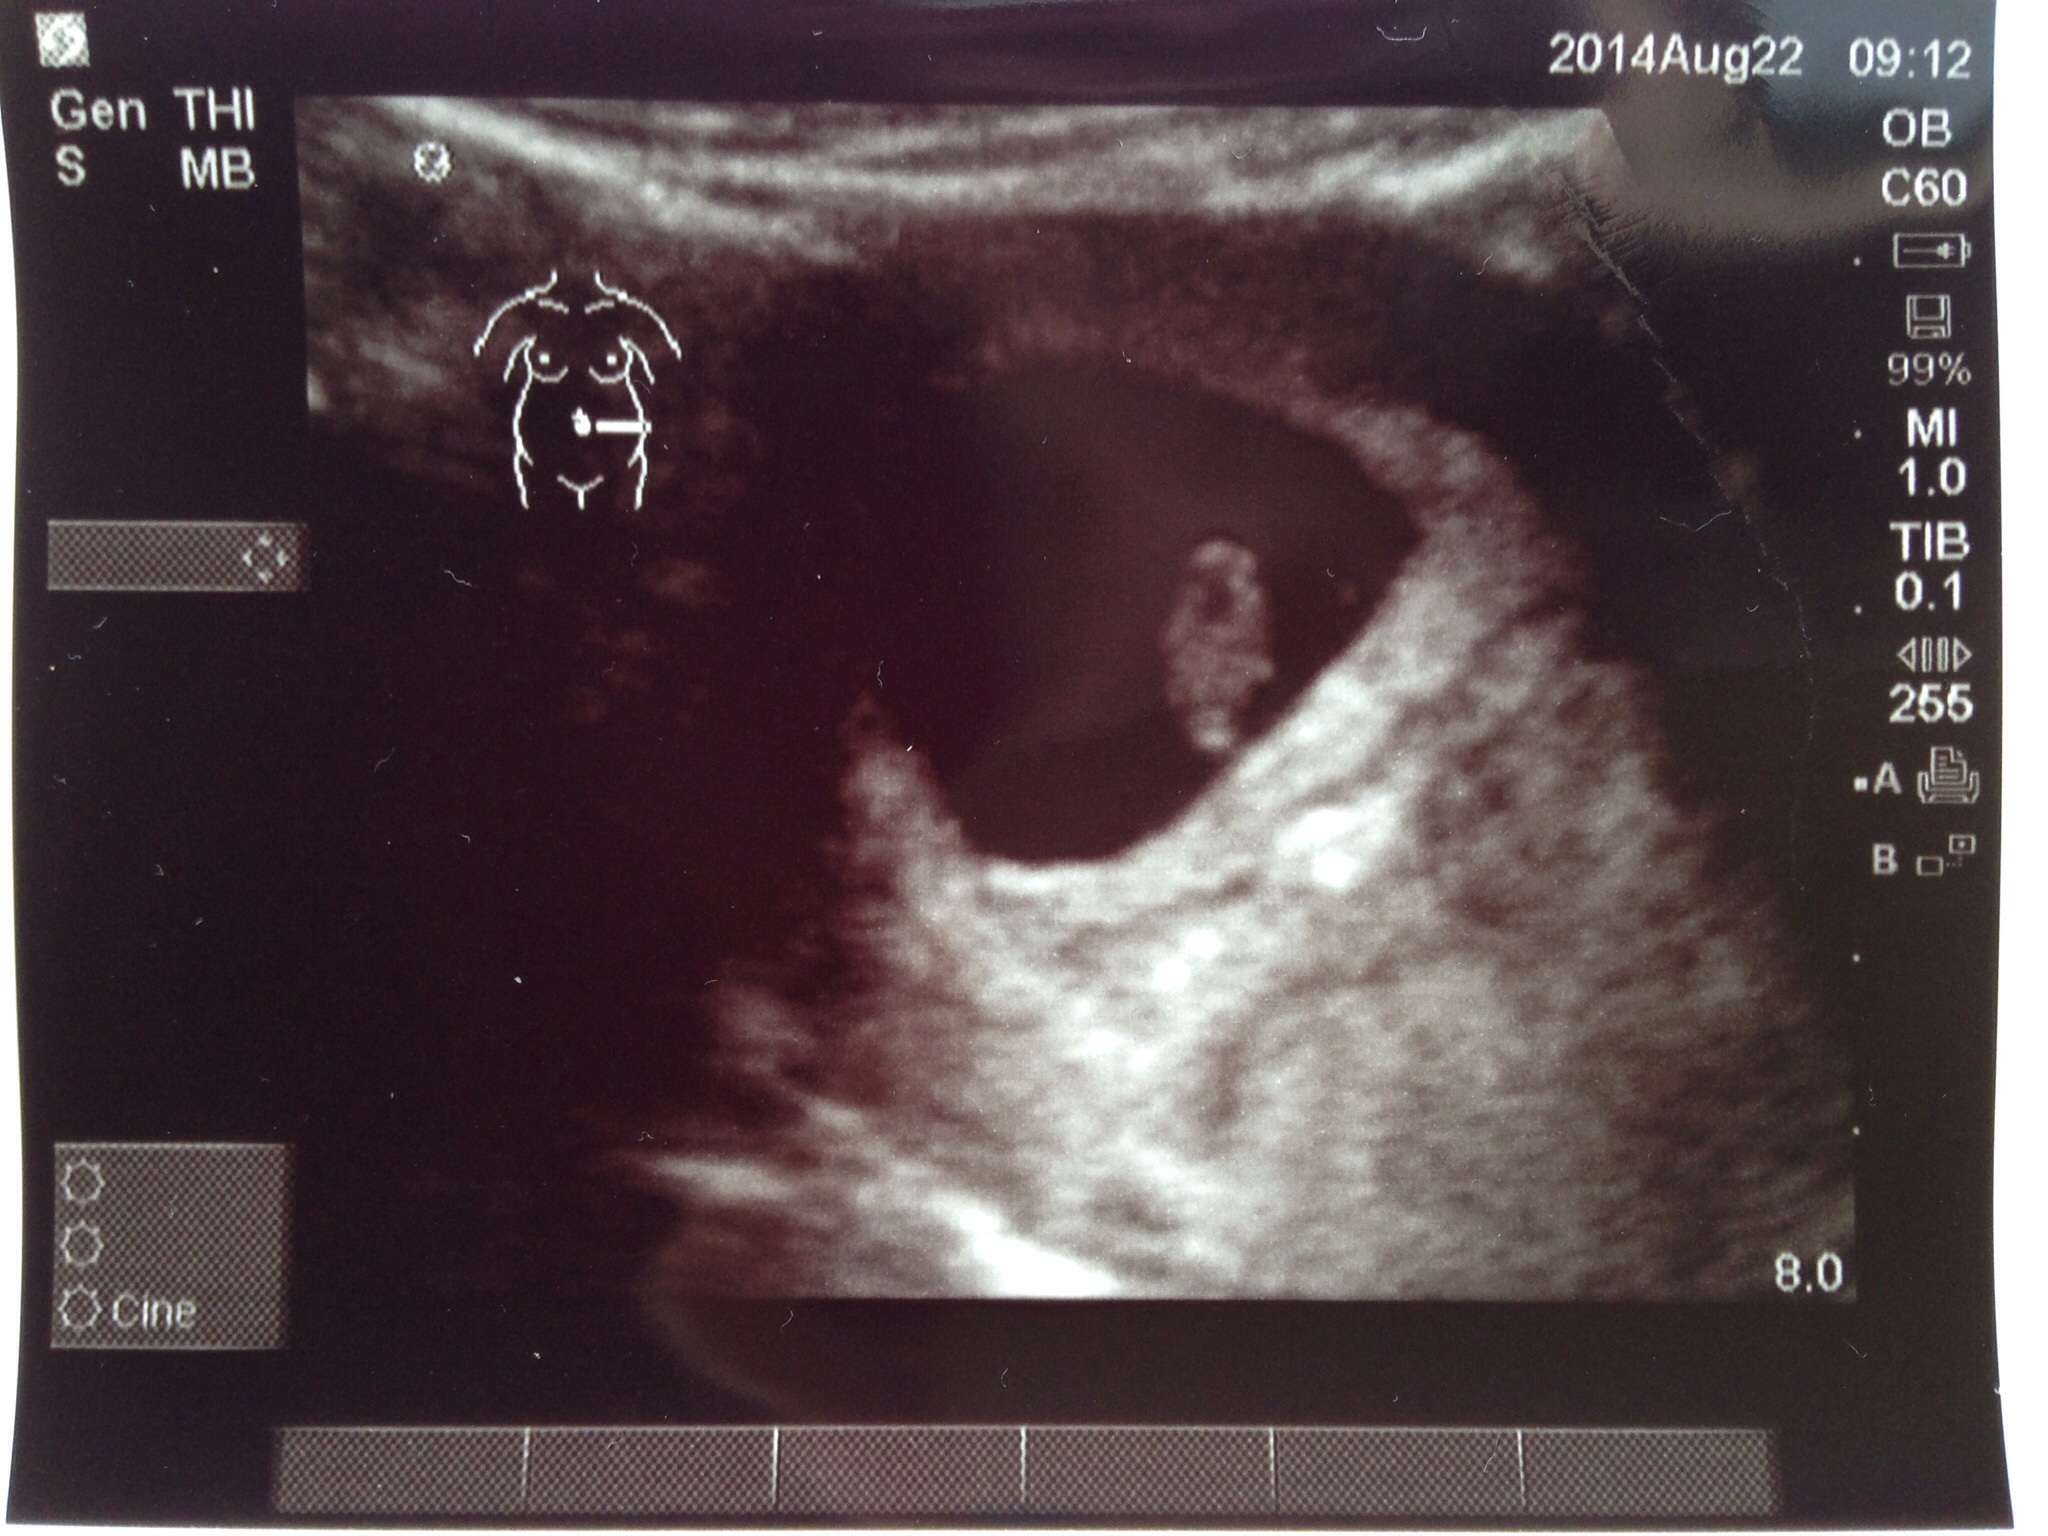

• I saw the heartbeat at 9 weeks exactly (8/27) it was 169!! It was my first prenatal appt so I'm set up in three weeks for another u/s, but the doc said the baby is measuring perfect and that's all I could hope for! Best wishes for all-healthy pregnancies